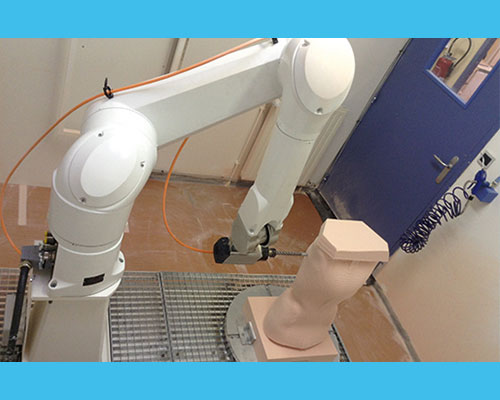

Positif (moulage) :

le moule positif est la reproduction originale du tronc du patient en 3D. Le positif sert pour le thermoformage de l’orthèse.